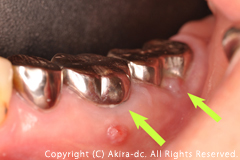

左下奥歯2本の歯ぐきから膿が出ています。 |

対合の歯が下がっていて不安定です。 |

左下奥歯の2本の歯根周囲の骨が著しく吸収しています。 |

左下奥歯の炎症により骨が吸収し、歯の動揺と膿みがでている状態でした。保存不可能と判断し抜歯させて頂き、2本のインプラント治療、対合歯の挺出(相手の歯が下がっている)の改善、小臼歯の審美修復(被せ物:ジルコニアクラウン)による左下奥歯の噛み合わせの改善をご提案しました。慢性的に、奥歯の周囲の骨が吸収とともに炎症を繰り返していました。その為、下顎に走行している神経の管に十分に配慮しながら治療計画をたてる準備をしました。そこで、3DCT画像診断のシステムを活用して3次元的に神経の走行や骨の欠損状態、インプラントの埋入位置、長さの選択などを考察し、システム画像上で十分にシュミレーションをして手術前のイメージを確実にして手術にあたることができました。快適に過ごすことができている様でうれしく思います。また、これを機会に歯の大切さや予防することの大切さをご理解頂き幸いに思います。